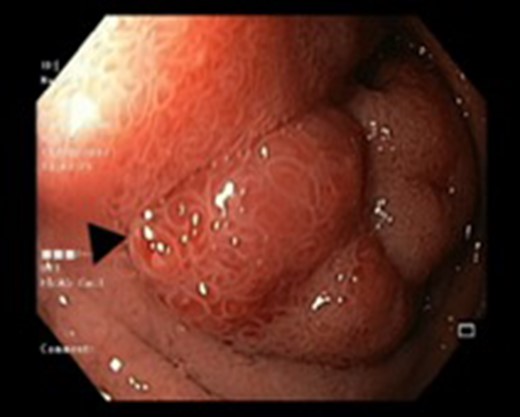

Endoscopic view of a submucosal mass in the second part of the duodenum.

| Case 1 | 30/M | 3 months | Vomiting, Malena | Well defined rounded hypodense submucosal lesion in second part of duodenum (Fig. 1) | Smooth mucosal bulge likely due to submucosal lesion in D2 with difficulty in negotiating scope beyond (Figs 2 and 3) | Normal duodenal mucosal fragments with mild lympho-mono nuclear cell infiltrate in the lamina propria | Pancreaticoduodenectomy | 2 | 2 days | 6 |

Endoscopy can localize the lesion; however, biopsies are usually negative. Only a deep endoscopic or a surgical biopsy provides adequate tissue because the Brunner’s gland proliferations are usually covered by normal mucosa [10] (Figs 6 and 7). It is prudent to include a Brunner gland hyperplasia in a differential diagnosis while evaluating a duodenal mass, since it has varied presentation and bleeding is a common clinical sign masquerading other gastrointestinal conditions, e.g. gastrointestinal stromal tumours.